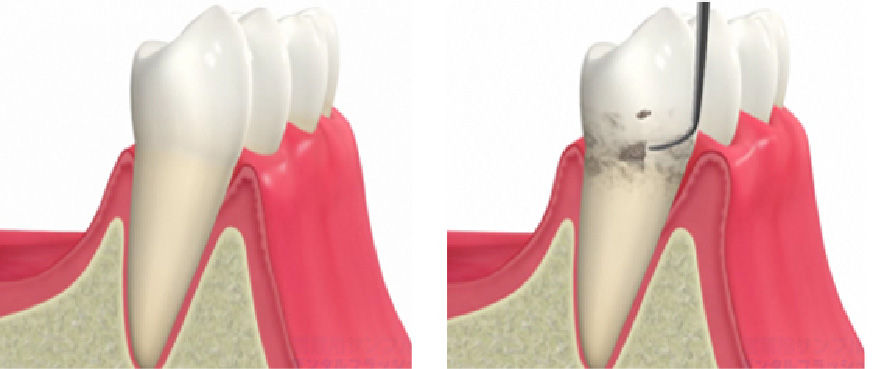

超音波チップを用いて歯周ポケット内のバイオフィルム(細菌の集合体)を除去します。歯周病菌は嫌気性菌であるため、酸素の届きにくい歯周ポケット内でバイオフィルムという形で増殖します。クリーニング後3~4ヶ月すると再びバイオフィルムが成熟し、歯周病を進める要因になってしまいます。こうした細菌を体の免疫力で抑えられる範囲にコントロールしておくことが、歯周病予防において最も重要です。歯周ポケット内のバイオフィルムはご自身の歯磨きでは除去することができません。毎日の丁寧な歯磨きやフロッシングに加え、3~6ヶ月に一度は必ずメインテナンスを受けましょう。